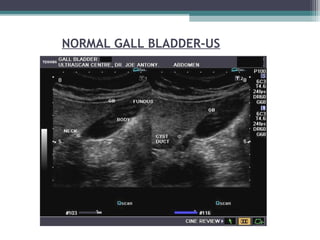

NORMAL GALL BLADDER-US

• 63.